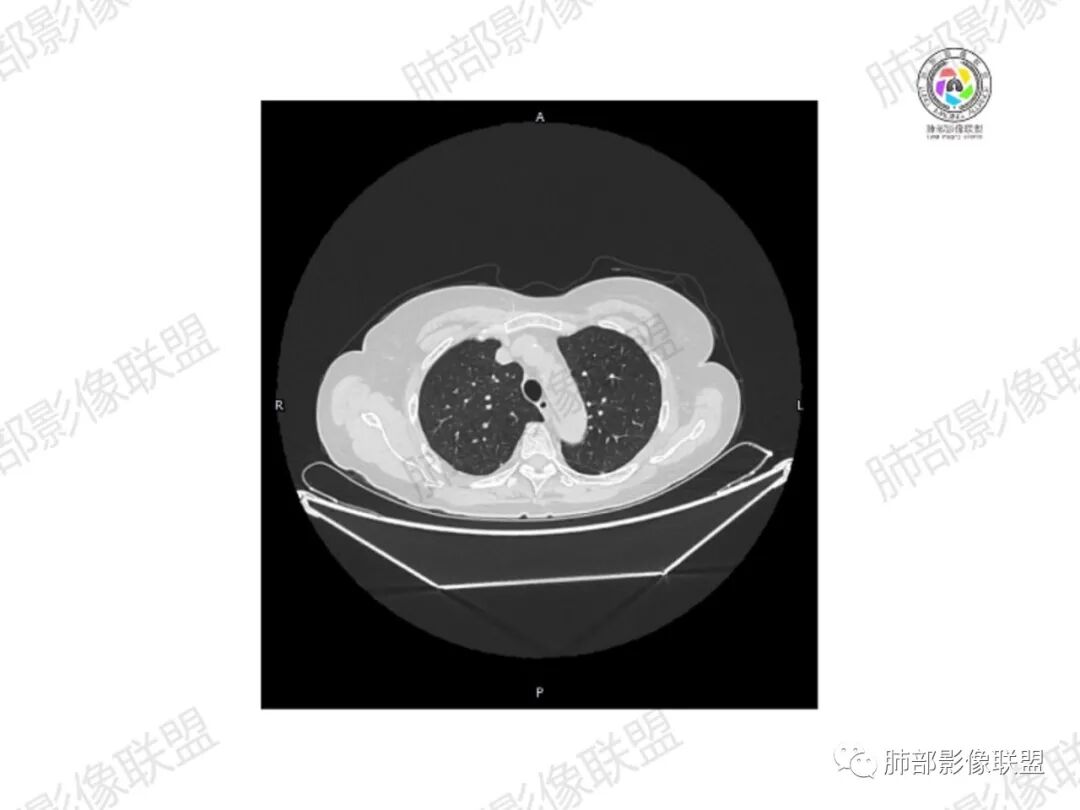

5.双肺多发类圆形结节影,边界清楚,随机分布,其间多见钙化密度影。

6.双肺门及纵隔未见肿大淋巴结。

3.双肺病灶符合转移瘤,伴有中央部分钙化者也以骨肉瘤转移较为多见。